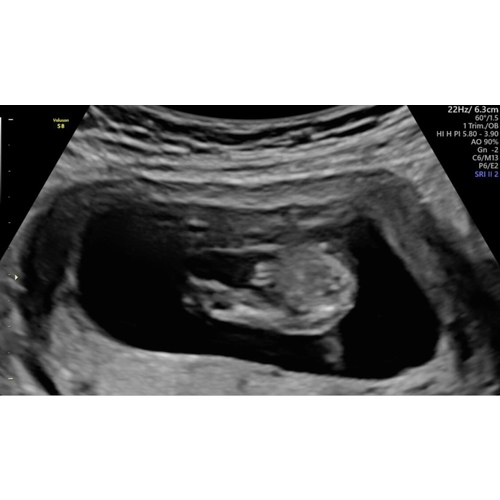

Goedemorgen, wat denk je bij deze echo? 14w

💗